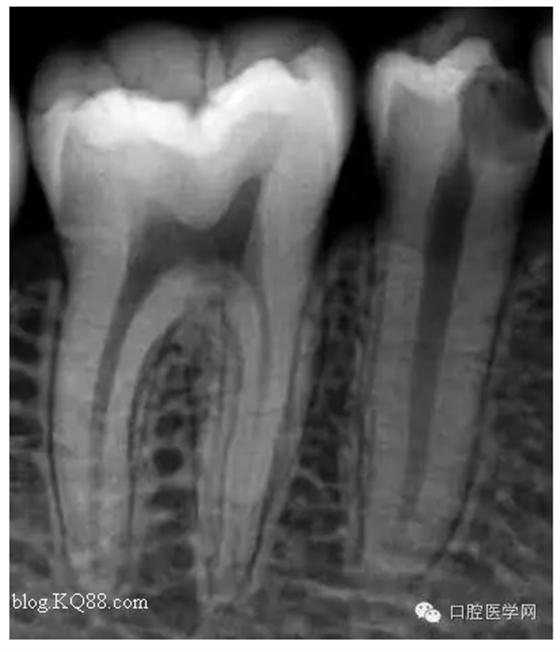

病人是我的助手,牙齒酸痛一周。吃冷熱時(shí)加重。無(wú)自發(fā)痛。先看看牙片

根據(jù)主訴:一過(guò)性冷熱痛無(wú)自發(fā)痛,X線:根尖無(wú)明顯改變應(yīng)診斷為深齲。小伙子平時(shí)愛(ài)吃冷飲最近冷飲是不敢吃了。